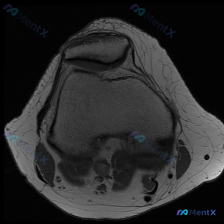

这是一份单张膝关节MRI轴位T1加权序列影像,临床怀疑存在软骨异常,要求读片分析。

- 骨性结构:髌骨形态完整,皮质连续,骨髓信号无异常;髌股关节对合关系大致正常,无半脱位;股骨远端滑车区形态轮廓正常,皮质光滑,骨髓信号正常,未见骨折、骨挫伤、骨侵蚀破坏。

- 关节软骨:髌骨后方关节面、股骨滑车关节面软骨信号对称,轮廓清晰,厚度均匀,未见局灶性缺损或变薄。

- 其他结构:视野内半月板未见异常;可见的股四头肌腱附着部、支持带等软组织结构无肿胀信号异常;关节腔无显著积液,滑膜无增厚,周围软组织无炎性渗出或包块。

这张T1序列对比度良好,解剖结构清晰,骨与软组织分界明确,未见局灶性异常信号,也没有软组织肿块、血管异常或皮下水肿。

单张轴位T1图像未发现明确的解剖结构异常或病理改变,当前影像结论为阴性,不支持本次观察范围内存在可见的软骨异常。